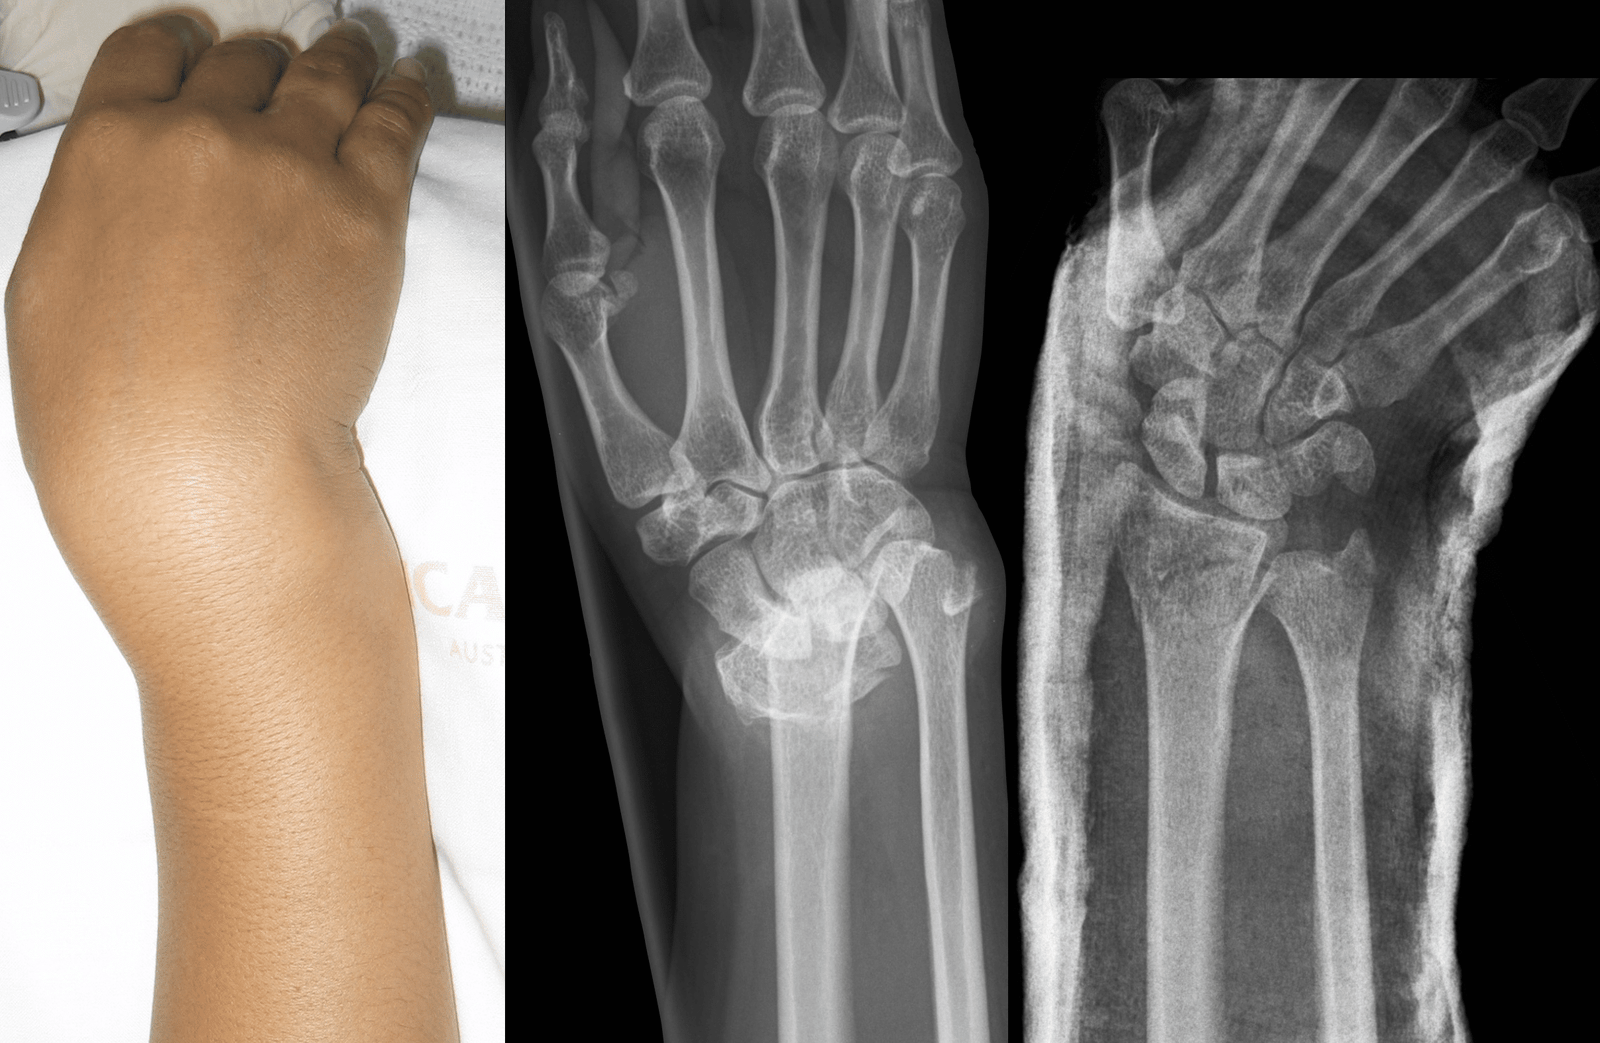

2) Swelling:

- Swelling may appear rapidly as a result of localizations of serous fluid.

- Swelling more in fracture than dislocations.

3) Deformity: Patient may unable to move affected part

Confirmation the diagnosis of fracture:

A) Special investigations :

1) X-ray: Commonly used.